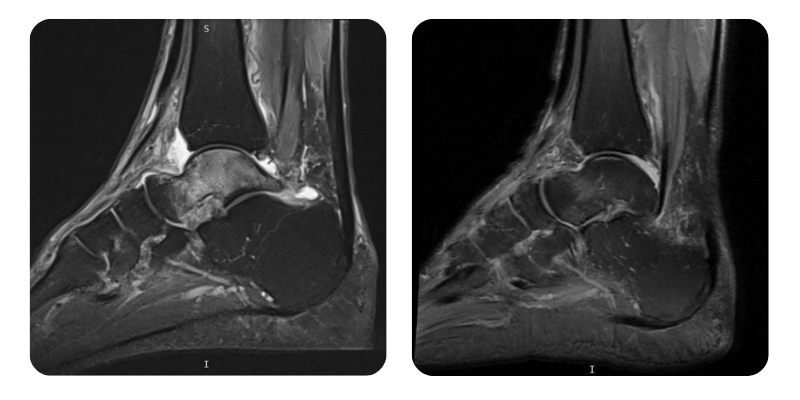

Înainte

După

T.F., 68 de ani - Necroză avasculară talus drept.

Anamneză: În urmă cu 3 luni pacientul a avut o fractură la nivelul epifizei distale peroniere drepte, care a fost tratată prin imobilizare gipsată. Ulterior după o lună pacientul a suferit o entorsă la nivelul gleznei și s-au asociat dureri la nivelul gleznei. Investigația RMN a stabilit prezența unei necroze aseptice la nivelul talusului. HTA sub tratament cu Preductal și adenom de prostată.

Diagnostic: Necroză avasculară talus drept.